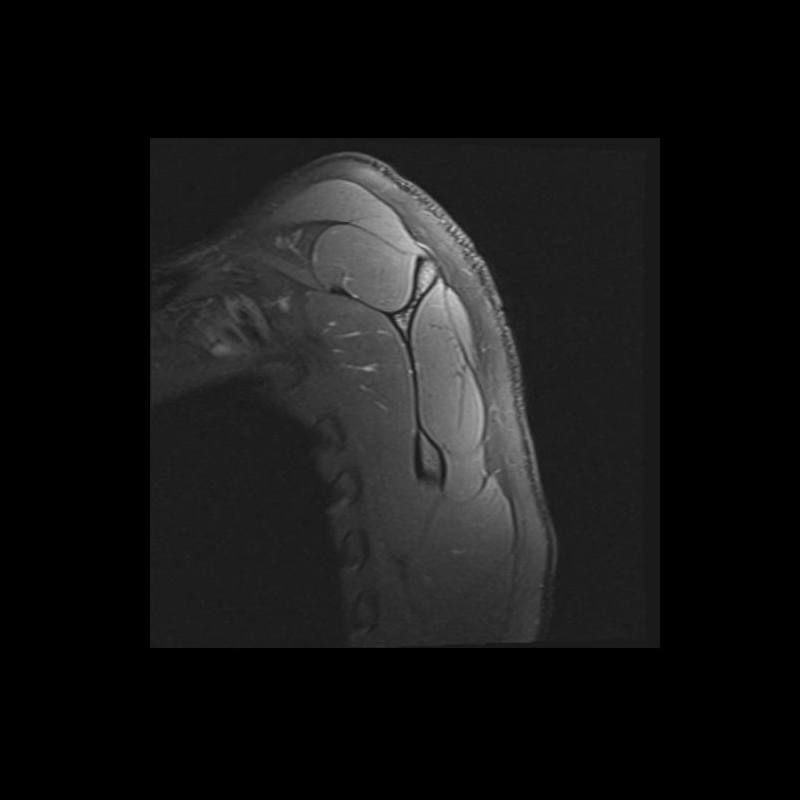

Shoulder MRI Anatomy